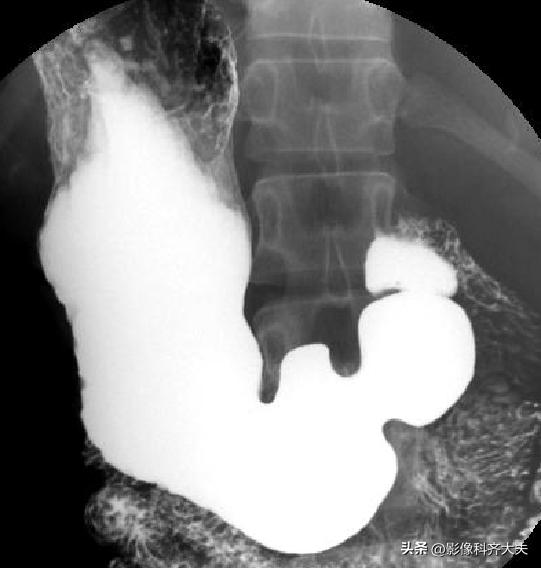

十二指肠球和圈充盈相

十二指肠球和圈双对比相

十二指肠球部及胃窦部加压相

全胃充盈相(站立位)